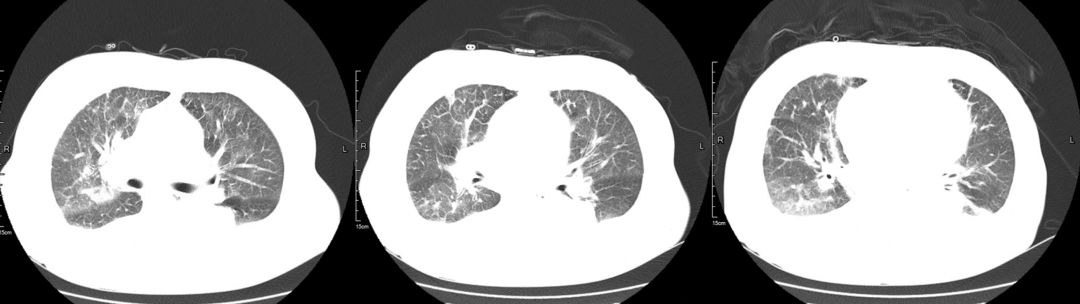

治疗后(2019-03-08)

患者咳嗽、胸闷症状明显缓解,3天后复查胸部CT提示肺部渗出影较前明显吸收。

3、辅助检查。胸部CT:双肺多发斑片状渗出性,部分实变,双侧胸腔积液。心超:左心增大伴中度二尖瓣关闭不全、主动脉瓣退行性变伴中度关闭不全、肺动脉高压伴轻中度三尖瓣关闭不全、房间隔膨出瘤(未破裂),EF 60% 正常。

肿瘤细胞浸润间质所致,咳嗽、咳大量粘液性泡沫性痰,病理可以明确鉴别。该病例中影像学表现密度相对均匀,与大叶性肺炎相比密度稍低,应用加强利尿3天后肺内磨玻璃影迅速吸收,变化快,肺部感染一般需2周甚至更长时间才能吸收,从影像特点及治疗后的反应上来讲均不支持肺炎。